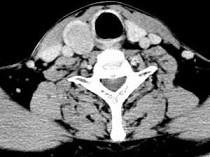

问题 男,43岁,右颈部扪及一包块,CT如图所示,应诊断为 ( )

选项 A、甲状腺原发淋巴瘤 B、甲状腺转移癌 C、甲状腺腺癌 D、结节性甲状腺肿 E、甲状腺腺瘤

答案 E